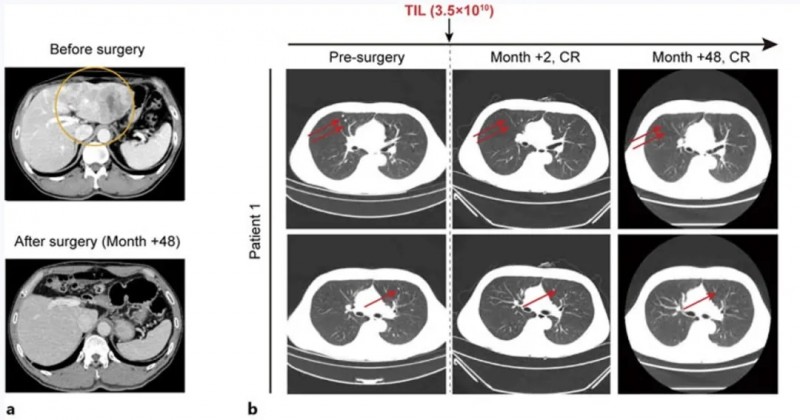

患者1是一位49岁男性,因肝细胞癌破裂入院。上腹部CT显示左肝叶多发病灶(最大病灶71×48mm),左侧门静脉充满肿瘤血栓;肺部CT发现多个结节。甲胎蛋白水平超60,500ng/mL,确诊为乙型肝炎病毒(HBV)相关性肝细胞癌,BCLC分期为C期。

患者入组I期临床试验(NCT03658785)后,先接受左半肝切除术,并获取肿瘤组织用于TIL培养。之后相继接受淋巴细胞清除方案(环磷酰胺+氟达拉滨)、TIL细胞回输治疗、白细胞介素-2(IL-2)治疗、两次托利普利单抗注射治疗。

结果显示:肝切除术后2个月,所有肺转移灶完全消失,至今(48个月)仍保持无瘤状态(详见下图a、b)。

▲图源“Liver Cancer”,版权归原作者所有,如无意中侵犯了知识产权,请联系我们删除